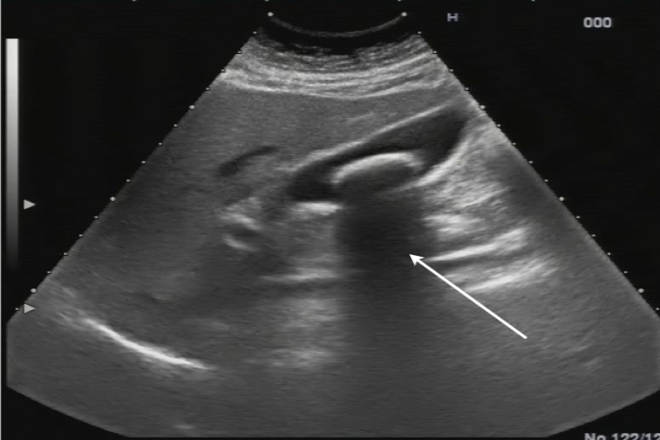

Ecografía hepática

Ecografía hepática El hígado es el órgano más grande del cuerpo humano, con un peso de aproximadamente 1500 gramos en adultos. Entre sus funciones se encuentra la contribución al mantenimiento de la homeostasis metabólica y al proceso de depuración de toxinas, además de recibir el retorno venoso del tracto gastrointestinal